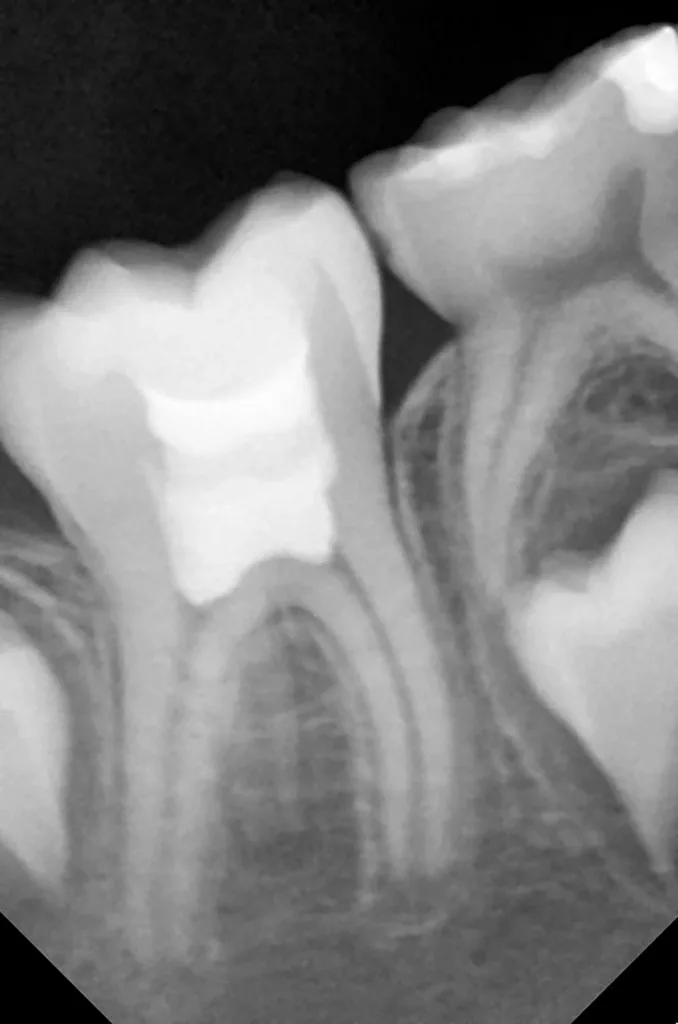

Bei routinemäßigen Röntgenkontrollen ergeben sich manchmal Zufallsbefunde unklarer Genese. So stellt sich beispielsweise bei der Betrachtung der Abbildung 1 die Frage, wie sich ein Zahnhartsubstanzdefekt so schnell entwickeln konnte. Ein weiteres Röntgenbild (Abb. 2), das vor dem Zahndurchbruch aufgenommen wurde, zeigt jedoch, dass es sich in diesem Fall nicht um Karies, sondern um die sogenannte präeruptive intrakoronale Resorption (PEIR) handelt. Für diesen Befund finden sich in der Fachliteratur auch noch andere Bezeichnungen wie „idiopathic external resorption of unerupted permanent teeth“ [1], „intra-follicular caries“ [2], „radiolucent lesions resembling caries“ [3], „occult caries“ [ 4] oder „pre-eruptive caries“ [5].

Das fünfjährige Mädchen stellte sich 2017 zur jährlichen Routinekontrolle vor. Im Rahmen der Untersuchung wurden Röntgenaufnahmen der Milchmolaren gemacht (Abb. 2). Der klinische und radiologische Befund der vor uns früher gelegten Kompositfüllungen war gut, es wurde allerdings eine PEIR an den noch nicht durchgebrochenen ersten bleibenden Molaren festgestellt (Abb. 2). Den Eltern wurde empfohlen, sich unverzüglich bei Beginn des Durchbruchs der ersten Molaren erneut zur Behandlung vorzustellen. Ein Jahr später erschien die junge Patientin schmerzfrei zur Kontrolle. Der Zahn 36 war noch teilweise mit Gingiva bedeckt. Auf einer neuen Röntgenaufnahme (Abb. 1) wurde die PEIR-Läsion mit unveränderter Größe in pulpanahen Bereichen bestätigt (Grad 3 der Läsion nach Seow). Der Zahnschmelz sah intakt aus, es konnte kein pathologischer periapikaler Befund bei den noch nicht ausgewachsenen Zahnwurzeln festgestellt werden. Daraufhin wurden die verschiedenen Behandlungsmöglichkeiten von Fissurenversiegelung bis Vitalerhaltung der Zahnpulpa mit den Eltern des Kindes besprochen.